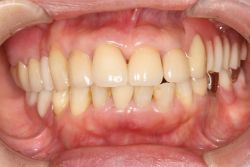

中間欠損 60代 女性中間欠損 MTC 2025.09.29 治療前 治療後 治療名称フレアアウト症例を単独冠と上下のMTコネクターで補綴し、機能と審美の回復を図った症例 アイヒナー分類B4期間–費用–治療内容–治療に伴うリスク– 30代 女性中間欠損(1・2本) MTC 前の記事 男性両側遊離端 MTC 次の記事